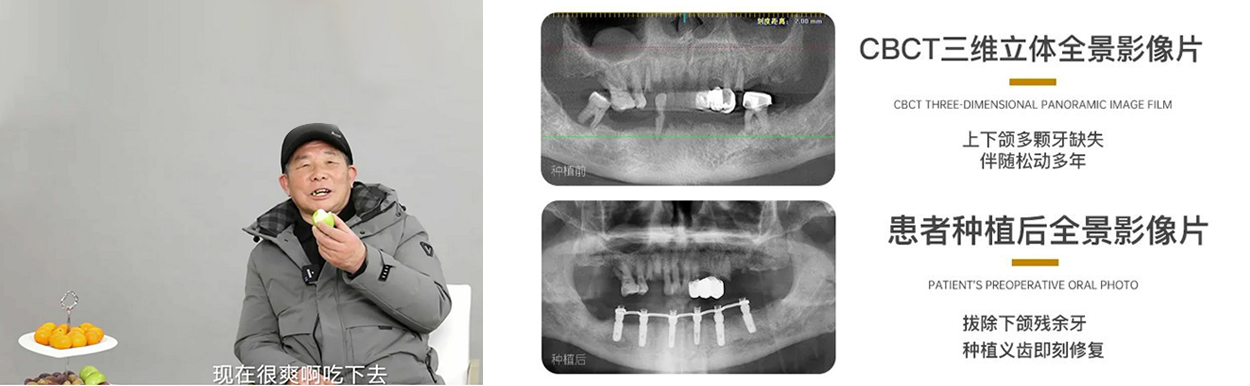

79岁高龄老人种植牙案例

口福是老人晚年最大的福报

老有健康,老有口福,对于这些高龄老人来说,就是福报。